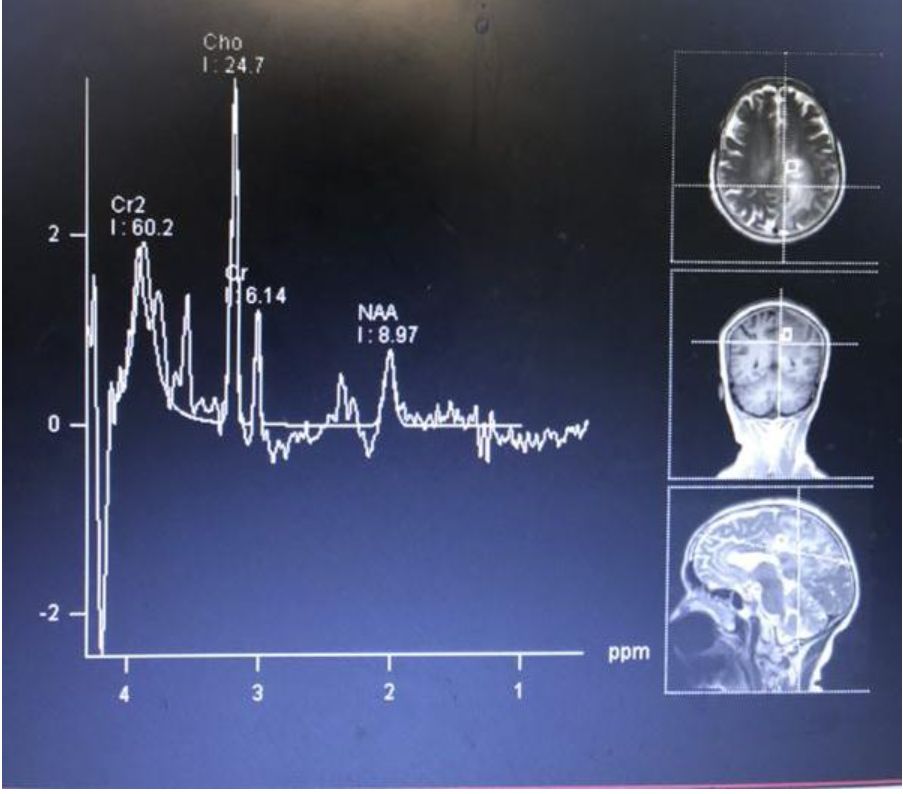

头颅MRI:脑萎缩、颅内多发或孤立肿块、脑膜浸润、灰白质交界处弥漫病变和脑积水等。占位效应和水肿可有可无。T1WI大小不等、形状不规则高信号,部分脑回变窄、脑沟增宽。T2WI可见多发大小不等片状高信号影,其内信号不均匀。FLAIR多呈高信号, DWI略高及等信号。SWI脑内可见多发类圆形大小不等圆形低信号影。增强:均匀、环状、斑片状强化。MRS:Cho增高, Cr、 NAA降低, Cho/ Cr>>1。